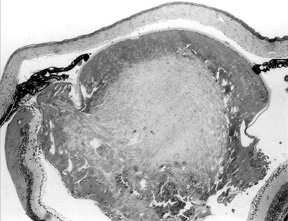

Figure 1a. Eye of To3/To3 homozygote, age 18 days.

The lens is vacuolated, and the lens capsule has ruptured.

The vitreous chamber is abnormally small.